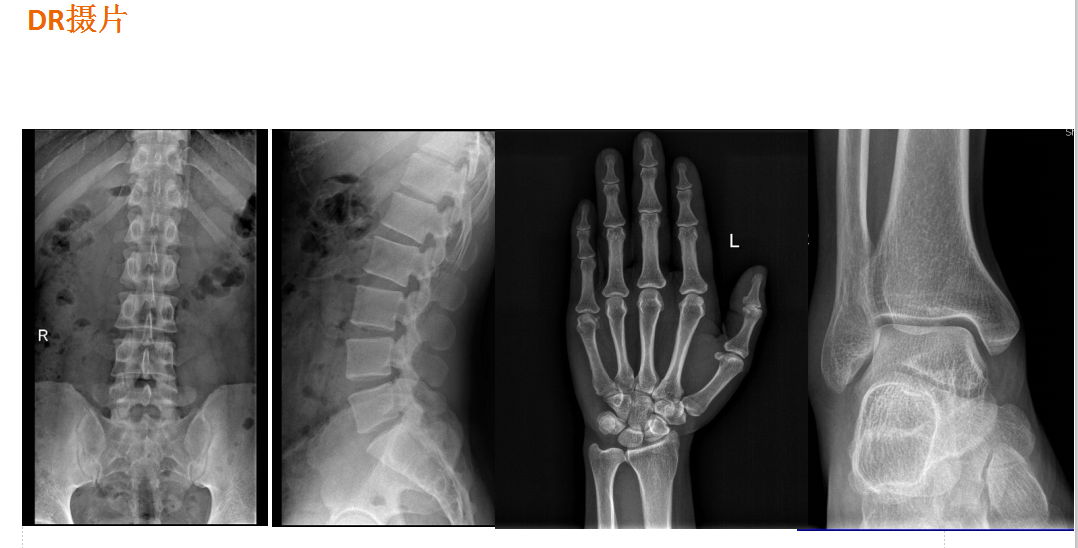

在全脊柱拼接摄影、全下肢拼接摄影方面,亦能弥补其他检查设备的不足。

下图为开展全下肢拼接摄影图像、全脊柱拼接摄影图像